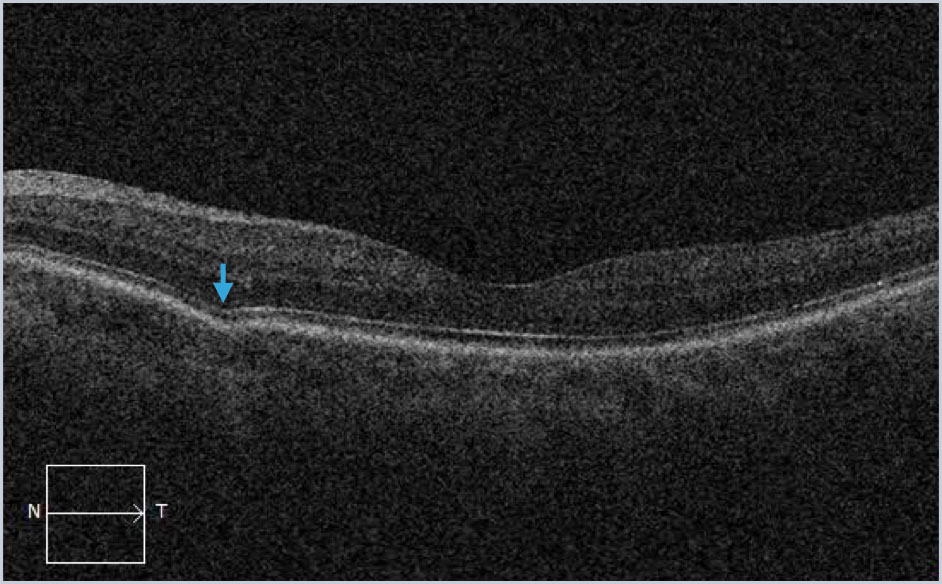

Focal choroidal excavation is commonly abbreviated as FCE and can be noted incidentally as well as in patients with an antecedent history of inflammatory chorioretinal disease.

Examples (blue arrows) from different patients with focal choroidal excavation. This finding is often noted incidentally and patients rarely have symptoms. Occasionally it can be associated with macular neovascularization and inflammatory disorders. The key visual sign on SD-OCT imaging is the outward bowing of the RPE.